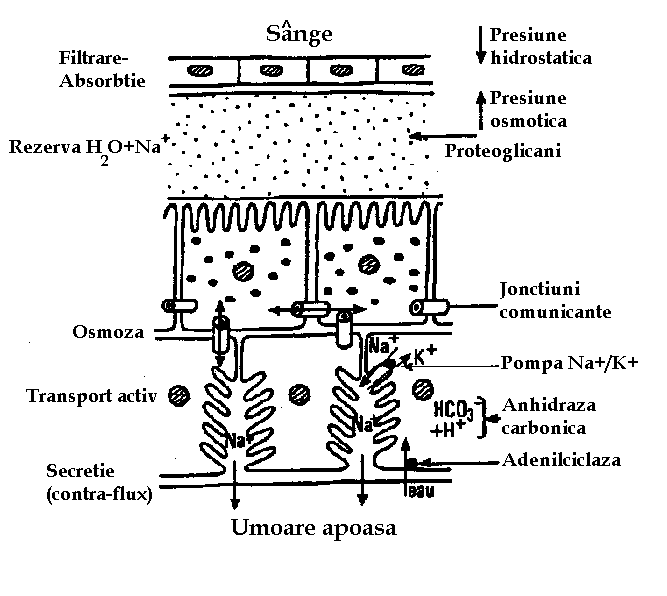

TENSIUNEA INTRAOCULARA SI GLAUCOMUL

TENSIUNEA INTRAOCULARA Glaucoamele grupeaza o serie de afectiuni diferite din punct de vedere etiologic si patogenic, caracterizate prin modificari caracteristice ale papilei nervului optic si ale campuCiteste tot ... 4780 cuvinte